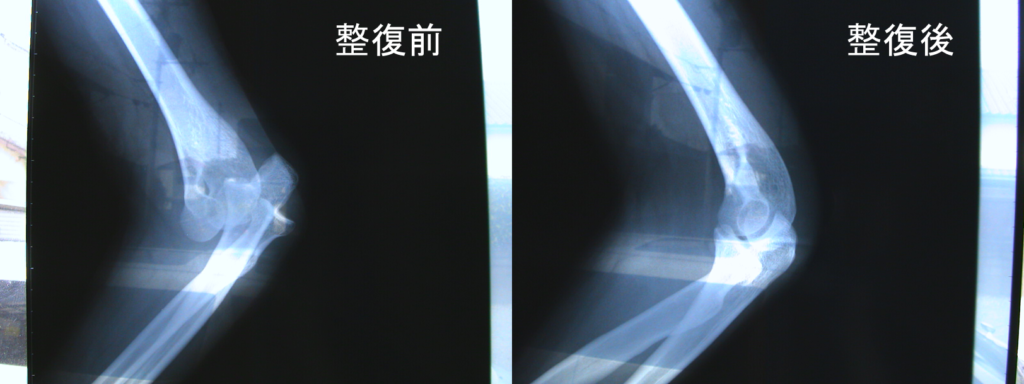

症例1)40代主婦、自転車で車道から歩道に乗り上げる際に、段差に前輪がすべり、地面に手を衝いて転倒。直後に激痛と肘関節運動が不能に。レントゲンをみると、左肘関節が脱臼をしていました。

この脱臼している関節をもとの位置に戻す処置を柔道整復と言いますが、

見事に処置は成功。ご覧の通りです。10日間ほどの固定で、

あとは関節運動やマッサージで元の機能(状態)に戻す回復治療をしました。